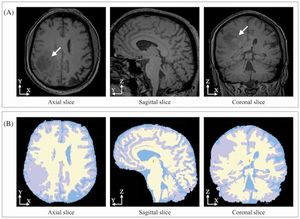

|

Publication: PLoS One. 2015 Dec 3;10(12):e0143821. PMID: 26633302 | PDF Authors: Gutierrez S, Descamps B, Vanhove C. Institution: Medical Image and Signal Processing Group, Ghent University-iMinds Medical IT department, Ghent, Belgium. Background/Purpose: Computed tomography (CT) is the standard imaging modality in radiation therapy treatment planning (RTP). However, magnetic resonance (MR) imaging provides superior soft tissue contrast, increasing the precision of target volume selection. We present MR-only based RTP for a rat brain on a small animal radiation research platform (SARRP) using probabilistic voxel classification with multiple MR sequences. Six rat heads were imaged, each with one CT and five MR sequences. The MR sequences were: T1-weighted, T2-weighted, zero-echo time (ZTE), and two ultra-short echo time sequences with 20 μs (UTE1) and 2 ms (UTE2) echo times. CT data were manually segmented into air, soft tissue, and bone to obtain the RTP reference. Bias field corrected MR images were automatically segmented into the same tissue classes using a fuzzy c-means segmentation algorithm with multiple images as input. Similarities between segmented CT and automatic segmented MR (ASMR) images were evaluated using Dice coefficient. Three ASMR images with high similarity index were used for further RTP. Three beam arrangements were investigated. Dose distributions were compared by analysing dose volume histograms. The highest Dice coefficients were obtained for the ZTE-UTE2 combination and for the T1-UTE1-T2 combination when ZTE was unavailable. Both combinations, along with UTE1-UTE2, often used to generate ASMR images, were used for further RTP. Using 1 beam, MR based RTP underestimated the dose to be delivered to the target (range: 1.4%-7.6%). When more complex beam configurations were used, the calculated dose using the ZTE-UTE2 combination was the most accurate, with 0.7% deviation from CT, compared to 0.8% for T1-UTE1-T2 and 1.7% for UTE1-UTE2. The presented MR-only based workflow for RTP on a SARRP enables both accurate organ delineation and dose calculations using multiple MR sequences. This method can be useful in longitudinal studies where CT's cumulative radiation dose might contribute to the total dose. |

Illustration of a CB-CT and five MR images of the same animal. a) Coronal CB-CT image and (b)-(f) biased field corrected and masked coronal MR images using a T1-weighted (b), T2-weighted (c), ZTE (d), UTE1 (e) and UTE2 (f) sequence. All CB-CT images were first co-registered using 3D Slicer version 3.6.3 by rigid body transformations using normalized mutual information. |